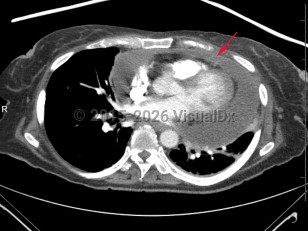

Aortic dissectionAortic dissection

Pulmonary embolismPulmonary embolism